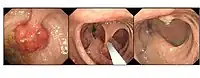

Polypectomy

Polyp is identified, snare is passed over stalk and polyp is then removed

Endoscopic polypectomy has been carried out since the early 1970s by both endoscopic snare removal and fulguration of polyps with hot biopsy forceps.[15][16]